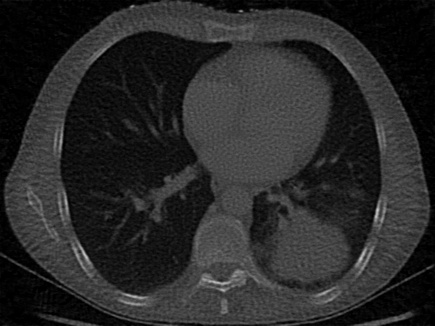

| Computed Tomography (CT) [28] | 2D | X-ray CT scan of a human chest, used to evaluate signal recovery in a classic underdetermined inverse problem. |

For CT experiments, we train models on a real chest CT slice from the dataset in Clark et al. [28], which was also used in WIRE [16]. The training data was 100 projection measurements of the original 326435 chest CT slice, forming a 100435 sinogram equivalent to approximately 30% of the total pixel count in the original image. Since this inverse problem is inherently underdetermined, we apply TV regularization in our Grid model. The TV hyperparameter was tuned using the classic Shepp-Logan phantom image [37] as a reconstruction target.